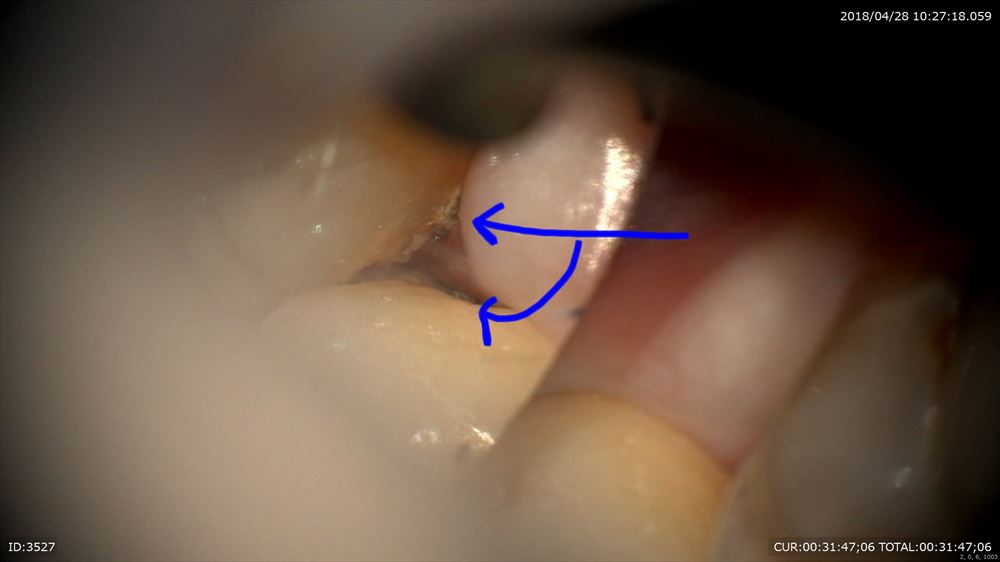

ここは6mmのポケット。必ずほら「歯石(細菌)」が付着。

で見て取れば

誰でも取れます。